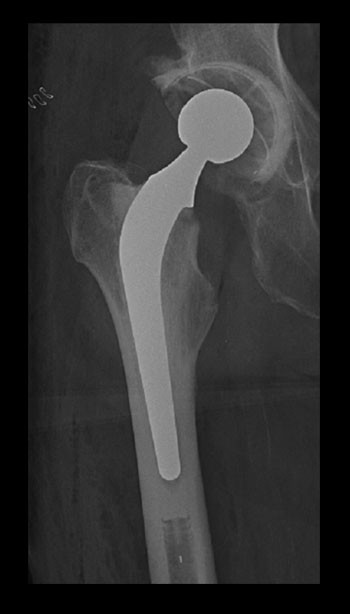

Protese settes i dag inn i mange ledd som behandling for artrose (fig 5). For albue og skulder er det utført færre proteseinngrep på indikasjonen artrose, og for ankel/fot må leddprotese for artrose anses som eksperimentell behandling. I 2008 registrerte Nasjonalt register for leddproteser 8 569 førstegangsproteser for idiopatisk artrose. Av disse var 5 321 i hofter, 3 094 i knær, 104 i skuldre og 50 i andre ledd (4). Av hofteproteseopererte blir ca. 10 % reoperert (med fjerning/utskiftning av hele eller deler av protesen) i løpet av de første ti årene, ytterligere 20 % blir reoperert 10 – 20 år etter primæroperasjonen (62). En tilsvarende andel av pasientene har et dårlig klinisk resultat, men er ikke reoperert (63). I Arbeids- og inkluderingsdepartementets invaliditetstabell er velfungerende protese i hofte eller kne tilordnet en invaliditet på 15 % (64).